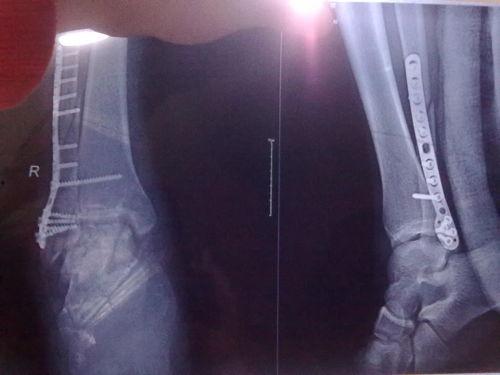

三、脚踝韧带撕裂的图片展示

下面是一些真实的脚踝韧带撕裂图片,让你直观地了解这种损伤。

四、脚踝韧带撕裂的诊断与治疗

1. 诊断:医生会根据你的症状和体征进行诊断,必要时还会进行X光或MRI检查。